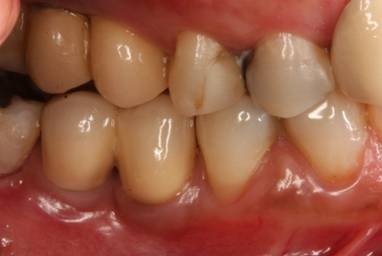

Figura 2. Vista clínica dos implantes, há 8 anos em função, instalados no lado direito do paciente (16/17 e  46/47). Observar a condição saudável do tecido mole adjacente aos implantes e da existência de espaço para higienização da prótese entre os implantes inferiores.